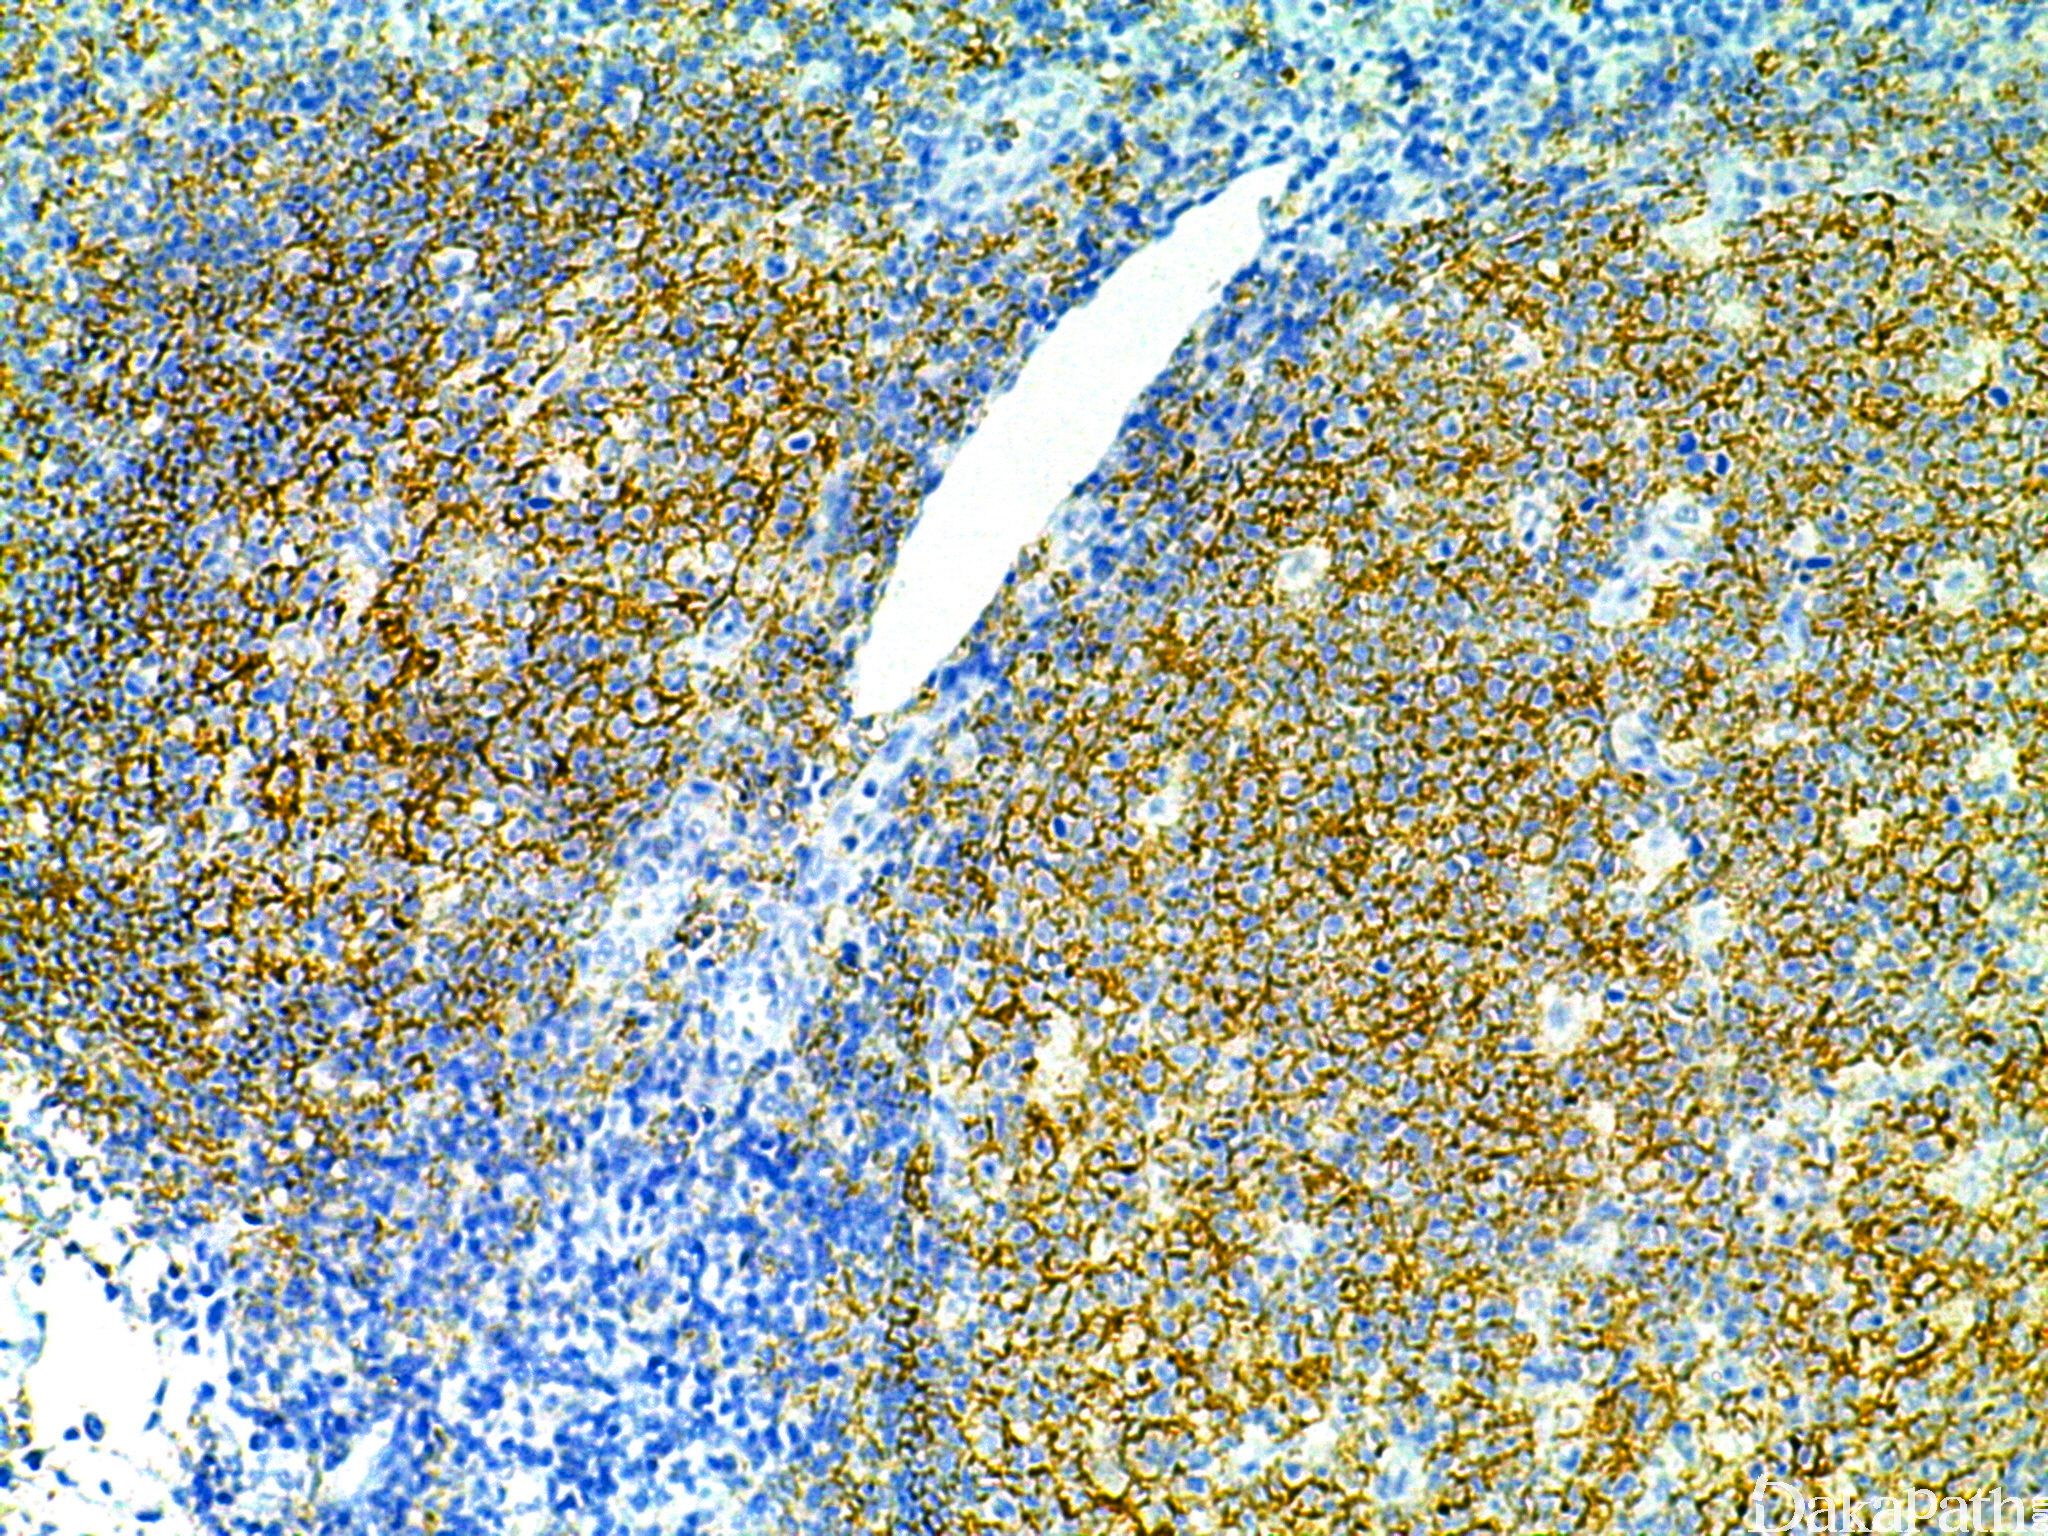

CD19

B 细胞共同抗原,表达于 B 细胞、滤泡树突细胞.

信号定位: 胞膜

B 细胞肿瘤的诊断,比 CD20 敏感;

浆细胞 CD19 阴性提示为肿瘤性增生.